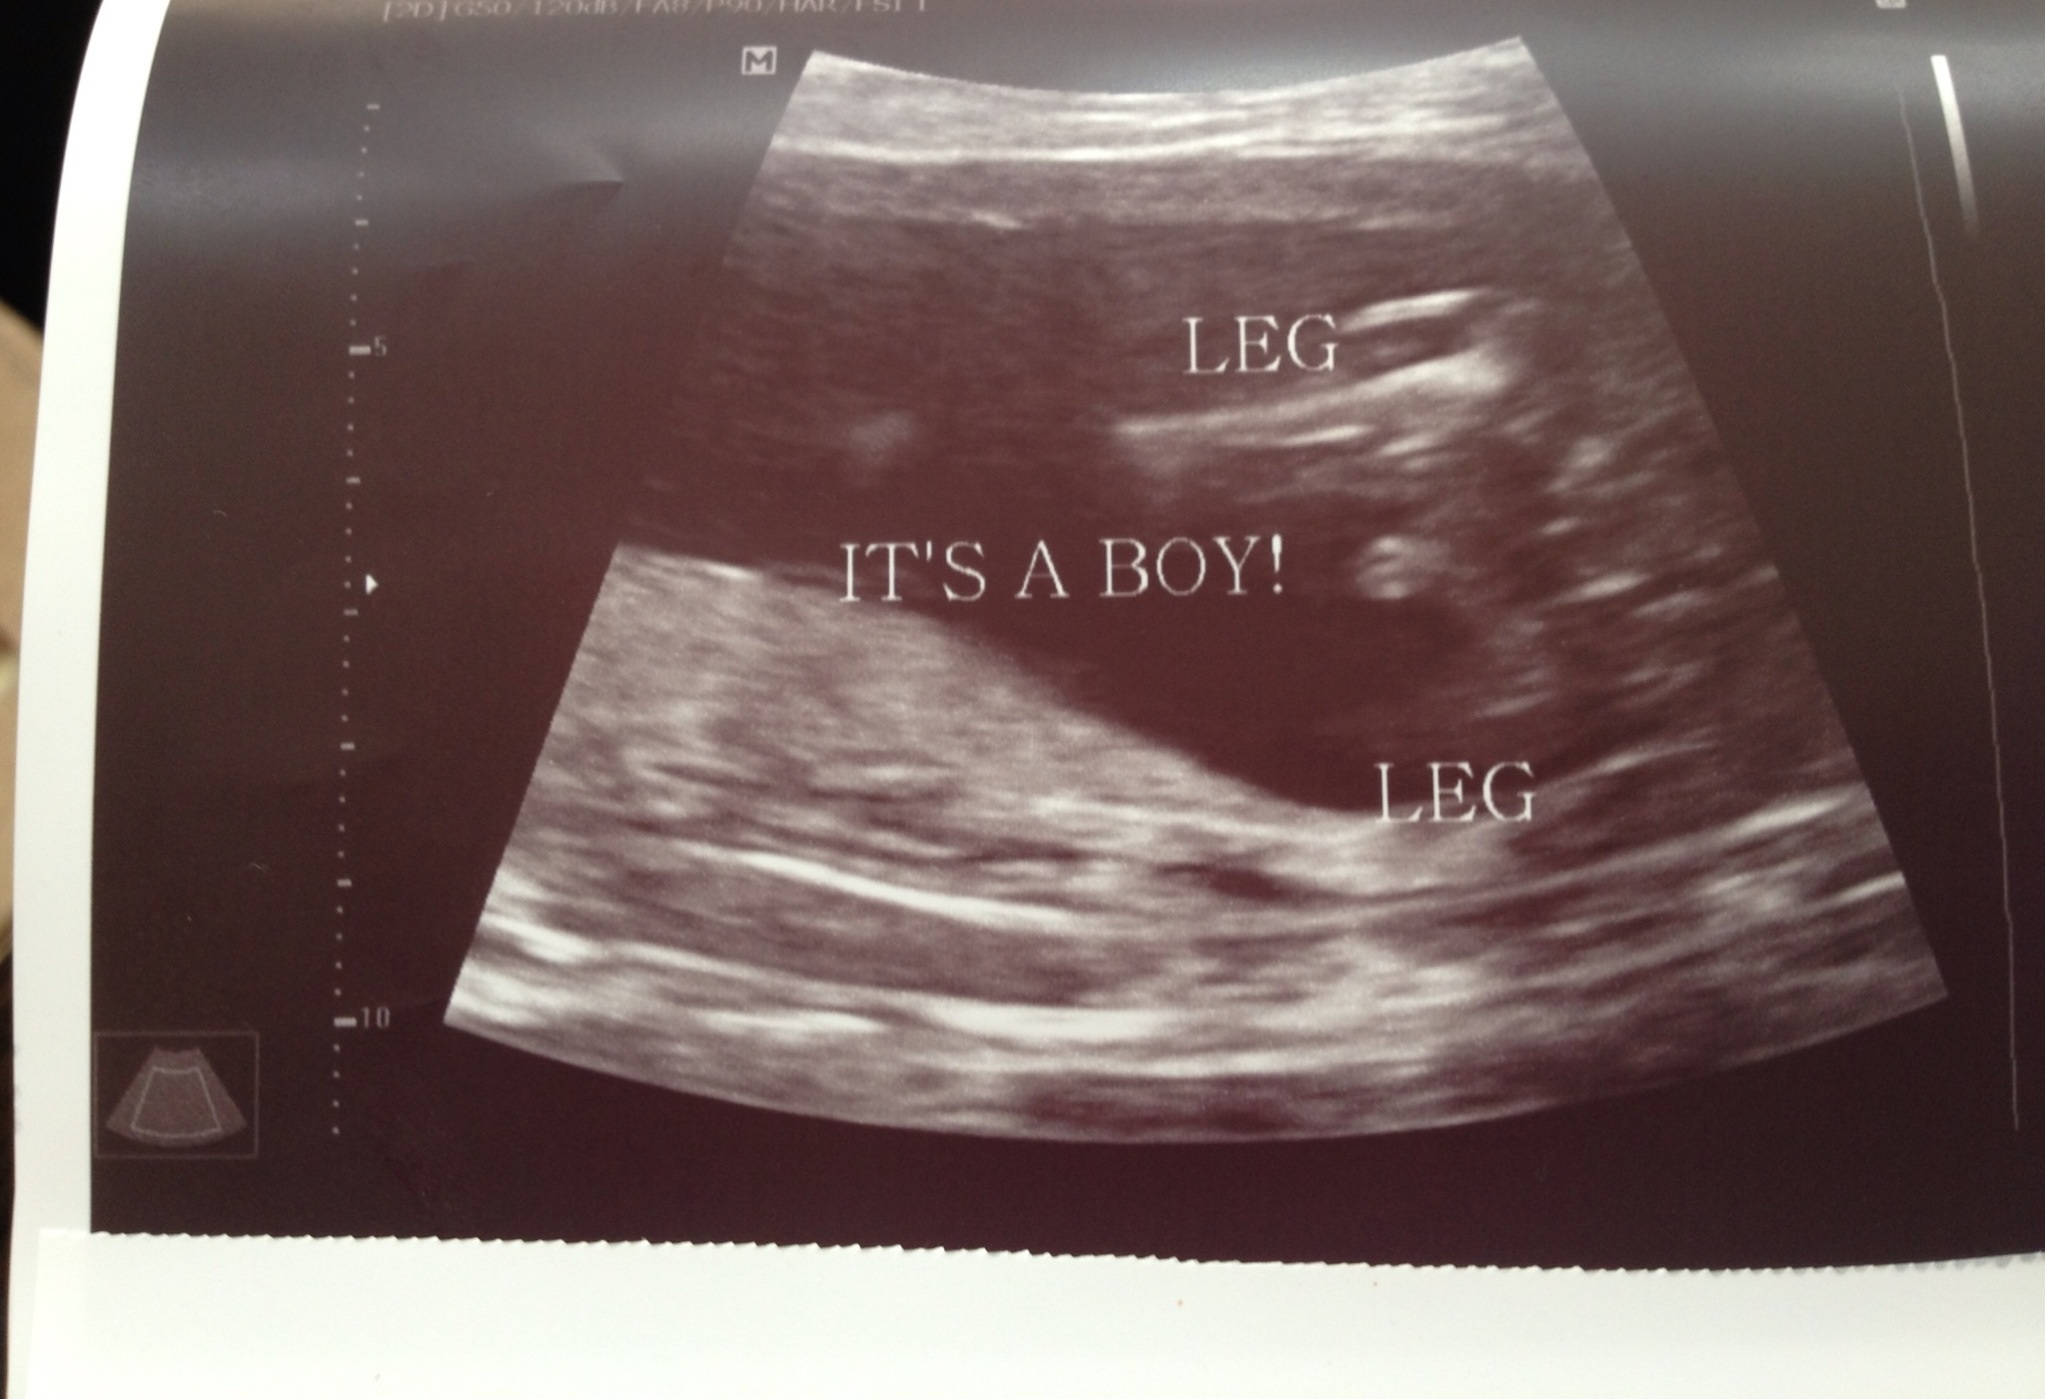

Today I had my anatomy scan and we are officially team BLUE!!! We finally told everyone today 18.1w after knowing the guess at the NT scan at 12 weeks, it was hard keeping it from everyone, but glad we waited until it was official. We are so happy everything went well and happy our first is a boy. I started feeling the baby move last week and it has gotten stronger and more frequent. Now I've started to feel him while standing too. What a great feeling. I can't wait until DH can feel it from the outside. H&H 9 months to all fellow bumps.